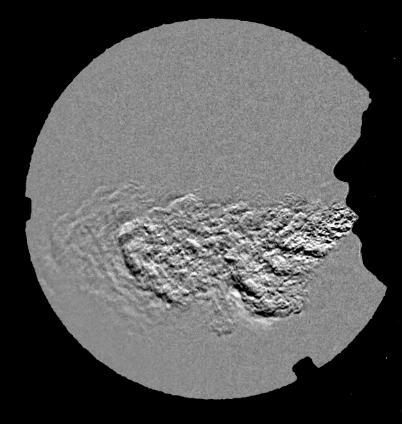

In April 2020, Professor Cahill therefore began investigating the problem of aerosol dispersion during surgery. Dr Nolan volunteered his time and expertise to this investigation, and his custom Schlieren facility was relocated to the old operating theatres of the Mater Hospital. Schlieren is a real-time optical technique, whereby local changes in the refractive index of air are made visible. In other words, by looking at how rays of light bend, this technique visualises human breath in the air in a striking way (see image below).